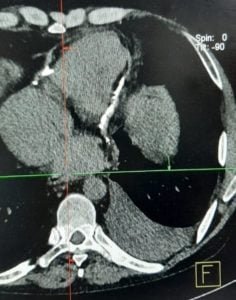

Image challenge : CT scan thorax

A young male presented with history of palpitations and shortness of breath of 3 weeks duration.He had gross ascites on examination . The CT scan thorax was done as shown below .What is the most likely diagnosis ?